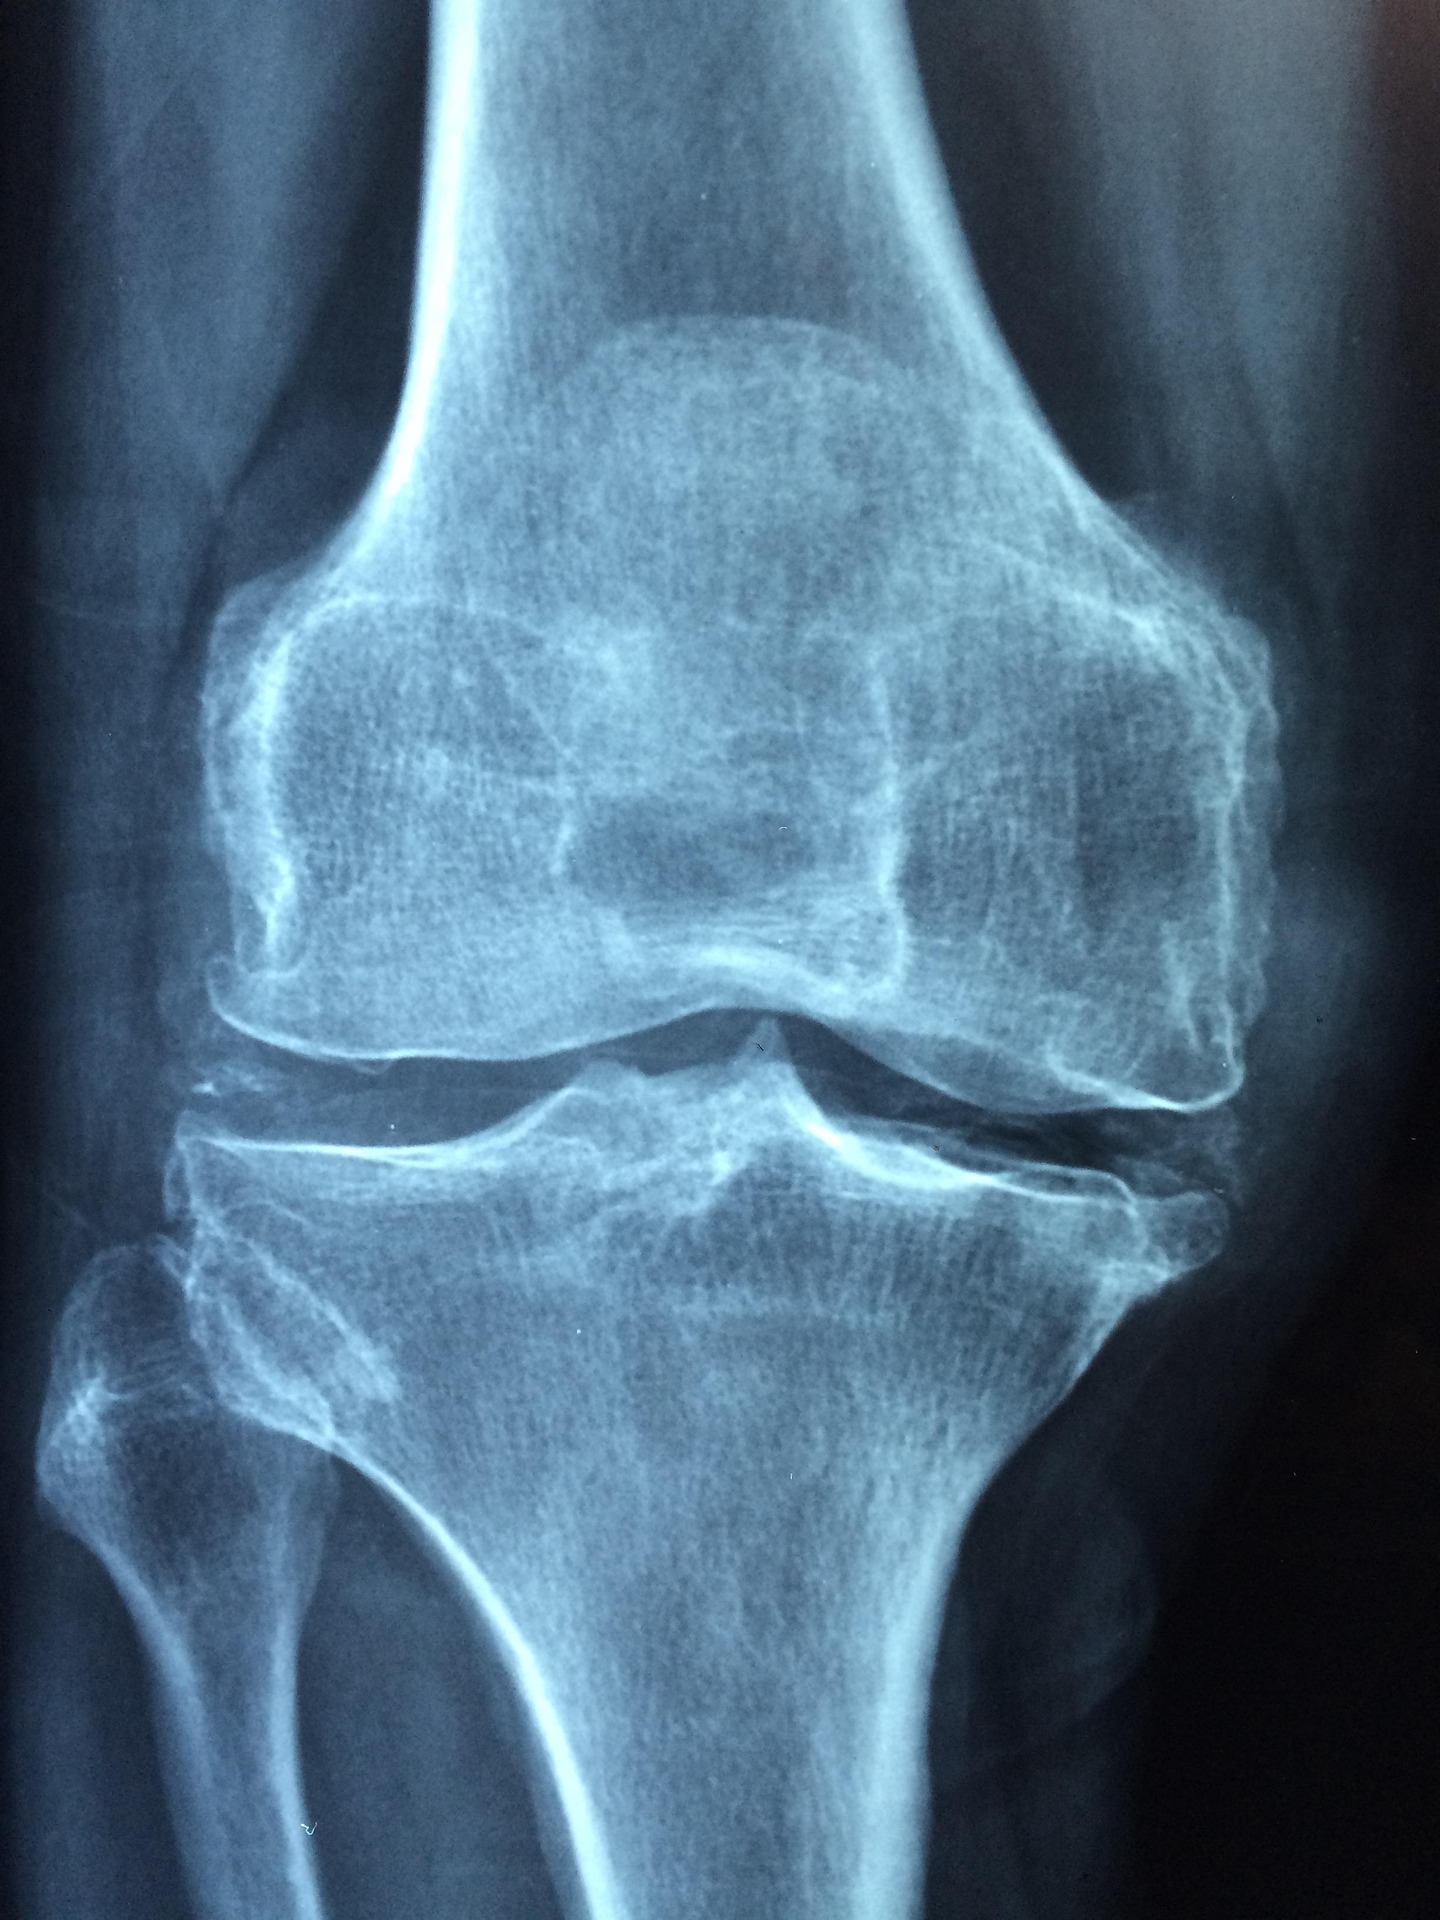

功能上的衰退则更为严重。王斌团队指出,衰老的骨髓间充质干细胞增殖能力显著下降,细胞周期几乎停滞,这意味着骨骼系统的自我更新与修复能力大幅减弱。最关键的分化能力也发生病理性偏移:成骨分化潜能下降,而成脂分化倾向增强,直接解释了为何衰老骨骼会出现“骨少脂多”的结构失衡。

骨骼系统由于富含干细胞巢和活跃的组织更新,可能对这类系统性衰老信号更为敏感。这也解释了为何在多种年龄相关疾病中,如糖尿病、心血管疾病和神经退行性疾病,患者常常同时伴有骨骼健康问题。